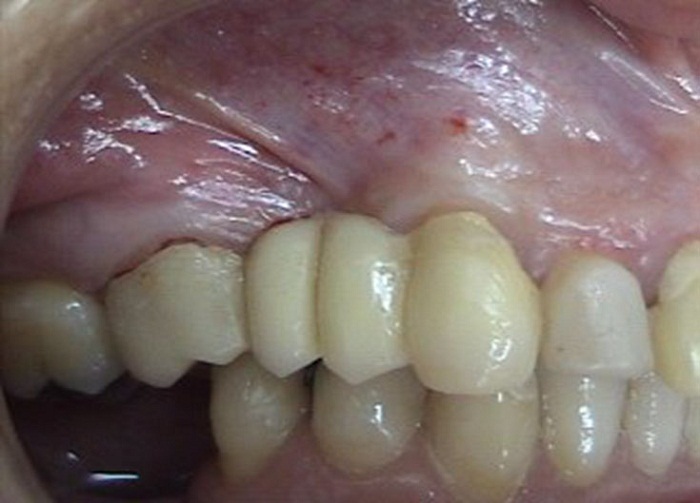

El caso corresponde a una mujer de 54 años de edad sin antecedentes médicos de importancia, a quien 12 años atrás le habían realizado una extracción de los dientes 15 y 14 (primer y segundo premolares superiores derechos, según la clasificación dígito dos). Clínicamente, se identificó una atrofia alveolar tipo I moderada vestibular del 14 y 15 con un adecuado grosor palatino. El rehabilitador decidió, con el consentimiento de la paciente, realizar una prótesis fija con pilares (dientes soporte) en los dientes 16 y 13 y pónticos en 15 y 14. Antes de la cirugía, se prepararon los pilares y se colocaron protecciones provisionales (figura 1).

Se le aumentó a la paciente el reborde alveolar por medio de la técnica de rollo modificada, pero sin incisiones verticales ni en vestibular o palatino. El procedimiento quirúrgico consistió en incisiones intracreviculares en los dientes 16 y 13, una incisión paracrestal palatina superficial desde mesial del 16 hasta distal del 13. A partir de dicha incisión se levantó la tapa epitelial palatina y se realizaron incisiones verticales mesial y distal y horizontal apical internas del tejido conectivo, el cual se elevó y enrolló en vestibular, donde previamente se realizó un colgajo mucoso (figura 2). El pedículo se enrolló hacia vestibular y se aseguró con puntos de sutura a cada lado. Finalmente, se suturó la tapa epitelial palatina. El diente provisional o temporal se recortó en la parte cervical para evitar el contacto con el tejido blando y se entregaron instrucciones posquirúrgicas por escrito a la paciente. Se le medicó con nimesulida de 100 mg, una tableta cada 12 h durante 3 días; azitromicina de 500 mg, una tableta diaria durante 3 días; y enjuagues con clorhexidina 2 veces al día por una semana. La paciente salió sin dificultades del consultorio.